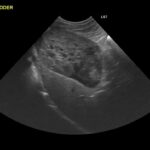

②超音波検査

超音波を用いて断片的に肝臓をみて評価する方法です。

下の写真の青線で囲っている部分が肝臓です。肝臓の形や腫瘍の有無、門脈体循環シャントがないか確認します。また胆のう内の胆汁の性状や胆管の状態を診ることもできます。